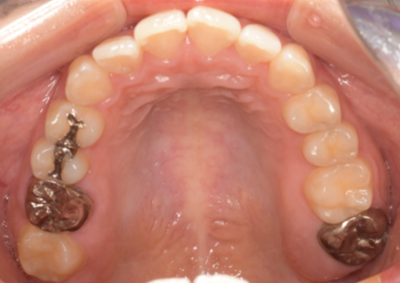

初診時口腔内写真

初診時パノラマX線写真と口腔内写真。

右上6に腫脹と排膿がみられた。

抜歯予定の歯と移植予定の歯

右上6(青丸)を抜歯し、右下8(赤丸)を移植することを計画した。

右上の抜歯後の治癒を待つため、抜歯の1ヶ月後に移植を行うこととした。